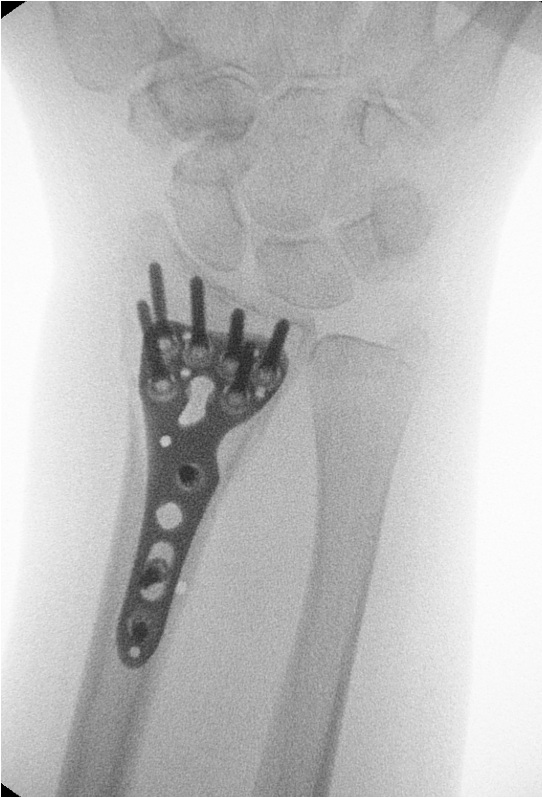

• Fracturas de muñeca

• Artrosis de la muñeca (postraumática, degenerativa o secundaria a lesiones previas)